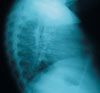

Because the patient had been born in a high-risk area, had a questionable history of blood transfusion, and had candidiasis and verrucae plana, immunodeficiency was considered. Additional laboratory studies were confirmatory. Levels of IgG were 2870 mg/dL (normal, 730 to 1500 mg/dL); IgA, 572 mg/dL (normal, 460 to 1200 mg/dL); IgM, 1117 mg/dL (normal, 50 to 240 mg/dL); antinuclear antibody, less than 40 (normal, less than 40); anti-double-stranded DNA, less than 10 IU/mL (normal, less than 10 IU/mL). She was HIV-positive. Tests for Mycobacterium avium-intracellulare (MAI) infection were negative, and her urine was negative for Cytomegalovirus. Chest films confirmed lymphocytic interstitial pneumonitis (LIP) (Figure 2). Further testing revealed that the child's mother was also HIV-positive.

Chest radiographs are essential in the diagnosis of LIP and may show bibasilar infiltrates, mediastinal widening, and hilar enlargement. Bronchoscopy with transbronchial biopsy is diagnostic. In patients who have documented HIV infection, cough, dyspnea, and classic infiltrates on chest films, LIP may be diagnosed clinically without any further invasive procedures.